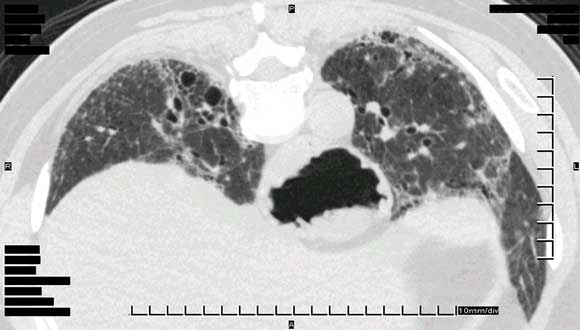

Pneumonitis was diagnosed based on clinical assessment, along with demonstration of interstitial infiltrates on high-resolution computed tomography and reduced transfer factor for carbon monoxide diffusion on lung function testing (Box 3).

We thank Dr R Spokes and Dr A Jones, Pathologists, and Dr C Hair, Pathology Registrar, Pathcare Consulting Laboratories, for preparing and annotating histological slides, and Dr D Lun, Radiologist, Barwon Medical Imaging, for providing the high-resolution computed tomography image.